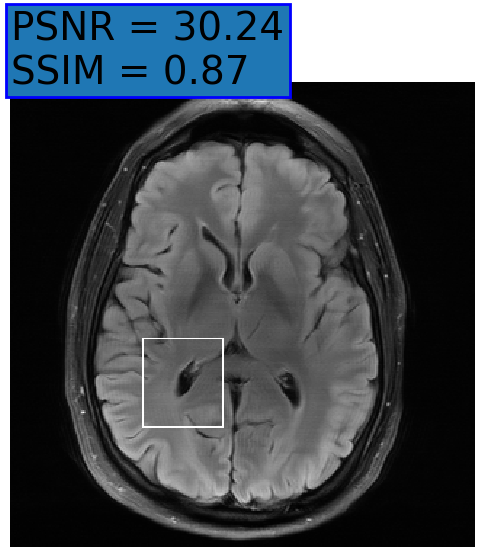

Figure 3: Examples of Reconstruction Results. Rows 1 and 3: The Ground truth (GT) fully sampled image, the reconstructed images obtained by the three models (1-3), NPB-REC, baseline, E2E-VarNet trained with Dropout, and the Std. map derived from our method for acceleration rates R=4𝑅4R=4, R=8𝑅8R=8, respectively. Rows 2 and 4: The corresponding annotated ROIS of the edema and resection cavity.

Fig. 3 presents examples of reconstruction results obtained by (1) our NPB-REC approach, (2) the baseline, and (3) Monte Carlo Dropout, for equispaced masks with two different acceleration rates R=4𝑅4R=4 and R=8𝑅8R=8. Table 1 presents the mean PSNR and SSIM metrics, calculated over the whole inference set, for the three models. our NPB-REC approach achieved significant improvements over the other methods in terms of PSNR and SSIM (Wilcoxon signed-rank test, pmuch-less-than\ll1e-4). The improvement in the reconstruction performance can be noted both quantitatively from the metrics especially for masks with acceleration rate R=8𝑅8R=8 and qualitatively via the images of annotations, where our results shows less smoothness than that obtained by Dropout.

A 4 r 30.04±6.78plus-or-minus30.046.78\mathbf{30.04\pm 6.78} 0.87±0.18plus-or-minus0.870.18\mathbf{0.87\pm 0.18} 29.91±6.87plus-or-minus29.916.8729.91\pm 6.87 0.867±0.182plus-or-minus0.8670.1820.867\pm 0.182 29.5±6.844plus-or-minus29.56.84429.5\pm 6.844 0.858±0.19plus-or-minus0.8580.190.858\pm 0.19